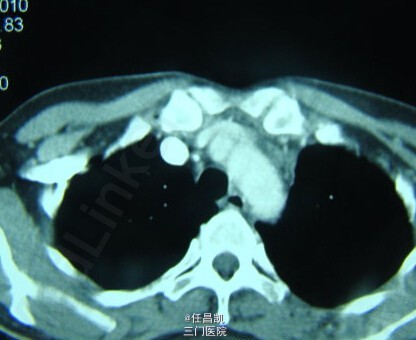

患者女,30岁,因胸闷不适4个月就诊,先后疑诊为肺癌、肺结核等治疗效果欠佳,进入我院。患者发病以来,无发热、咳嗽、血痰、胸痛等。

查体:心肺听诊无异,未见阳性体征。 辅查:CT如图所示。

入院诊断:肺部肿块待查 处理:入院后行手术探查+切除术治疗,术中快速病理检查排除恶性肿瘤,切除病灶,病理和免疫组织化学检查诊断为巨大淋巴结增生症。术后予补液、营养支持等对症处理,患者恢复顺利,复查CT无异,症状缓解遂出院。 出院诊断:胸内Castleman病